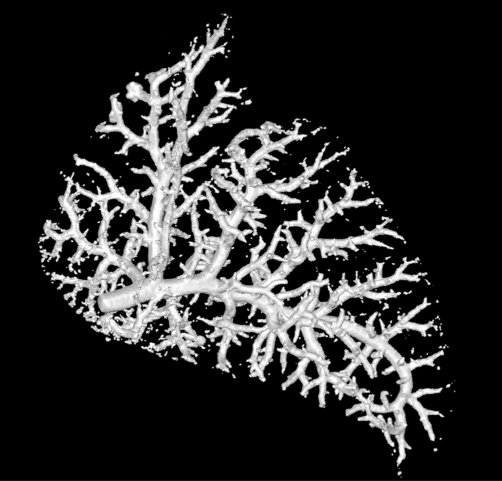

For this bogpost, we will look at the blood vessels inside of a lung. This data was shared with us by Marcus Kitchen, Andrew Stainsby, and their team of collaborators.

This research group focusses on lung development. We want to compare the blood vessels in a healthy lung, against a lung from a hernia model. In the hernia model the lung is underdeveloped, squashed, and smaller.